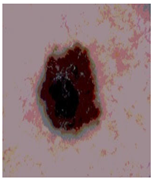

![]() | ![]() | ![]() | ![]() |

| Img1 | --- Pixel Intensity (0–255) ---> | ||

| Img2 | --- Pixel Intensity (0–255) ---> | ||

| Img3 | --- Pixel Intensity (0–255) ---> | ||

| Img4 | --- Pixel Intensity (0–255) ---> | ||

| Img5 | --- Pixel Intensity (0–255) ---> | ||

| Img6 | --- Pixel Intensity (0–255) ---> | ||

| Img7 | --- Pixel Intensity (0–255) ---> | ||

| Img8 | --- Pixel Intensity (0–255) ---> | ||

| Img9 | --- Pixel Intensity (0–255) ---> | ||

| Img10 | --- Pixel Intensity (0–255) ---> | ||